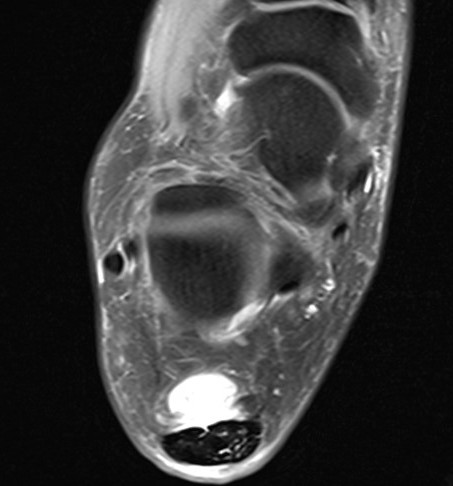

MRI

Retrocalcaneal bursitis with Haglund's

Partial tearing at insertion with retrocalcaneal bursa

Tendon thickening, Haglund's deformity and retrocalcaneal bursa

MRI grading

- Grade I: 6 - 8 mm thickening

- Grade II: > 8 mm tendon thickness with < 50% tendon degeneration

- Grade III: > 8 mm tendon thickness with > 50% tendon degeneration